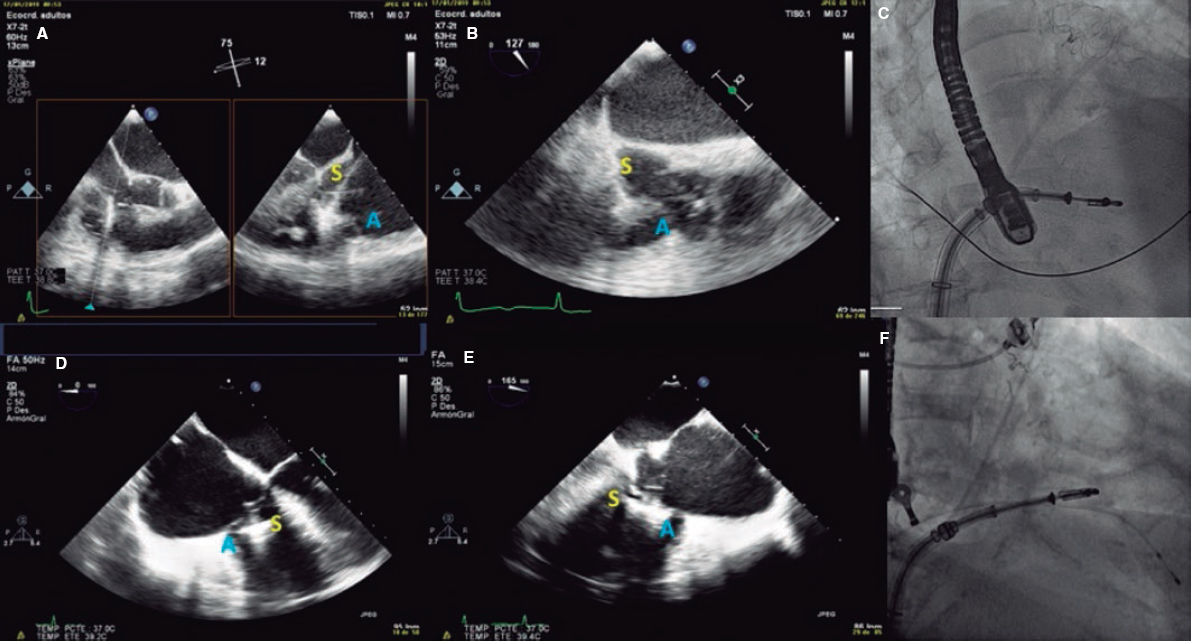

5. When the clip remains perpendicular on the TV, the GC clockwise rotation will move the clip towards the septal position. The GC counterclockwise rotation will move it towards the lateral region. The stabilizer advancement will bring the clip closer to the A-S commissure. After retraction, it will pass to the P-S commissure. This will allow complete range of motion and guarantee the correct location of the grasping (figure 5).

Figure 5. A: transesophageal echocardiogram in 3D zoom mode; periprocedural frontal view. The guide catheter can move inside the right atrium towards the aortic valve by advancing the entire system (red arrow) or towards the posterior leaflet by retracting it; the movement towards the septum (blue arrow) is possible through clockwise rotation of the guide catheter, and towards the right ventricle free wall through counterclockwise rotation. B: explanted heart, anatomic view. A, anterior; Ao, aorta; P, posterior; S, septal; CS, coronary sinus.

6. When the desired position has been achieved, the clip opens and perpendicularity is assessed. This should be done by using a 2D TEE in the transgastric short axis or by 3D zooming in the atrial view. The clip should be rotated smoothly so that it remains completely perpendicular to the desired grasping site (figure 6 and video 3 of the supplementary data).

Figure 6. With the clip on the tricuspid annulus the transgastric short axis (A) or 3D zoom (B) should be used to steer the clip. A, anterior; Ao, aorta; S, septal.

8. Back in the RV, the perpendicularity of the clip with respect to the target coaptation line should be confirmed on the transgastric short axis view. Then, the grasping view should be looked for, that is, the view that better shows the target leaflets and the clip with wide open arms. It is essential to have good ultrasound imaging during grasping to guarantee the correct insertion of the leaflets and the perpendicularity of the arms of the clip. Repeated suboptimal captures of the leaflets should be avoided to not cause excessive damage (TV leaflets are thinner and more fragile compared to the mitral valve leaflets) (figure 7).

Figure 7. Examples of grasping view. A and D: patient 1, grasping from the intercommissural view at 75° and from the direct grasping view at 125°. B and E: patient 2, direct grasping view acquired at 0° and 160°. C and F: right, anterior, oblique projection to steer the movement of the clip. A, anterior; S, septal.

9. Once the leaflets have been captured, their insertion should be confirmed through multiple 2D TEE views. Also, the presence of tissue bridges should be verified (though 3D TEE views). Multiplane is very useful for assessment purposes. A TTE or an intracardiac echocardiography should be used in cases of uncertain leaflet insertion. The TV mean gradient should be measured to discard stenosis; in general, mean gradients > 3 mmHg are not recommended (figure 8).

Figure 8. A-D: grasping assessment in multiple views for leaflet insertion assessment and reduction of tricuspid regurgitation.